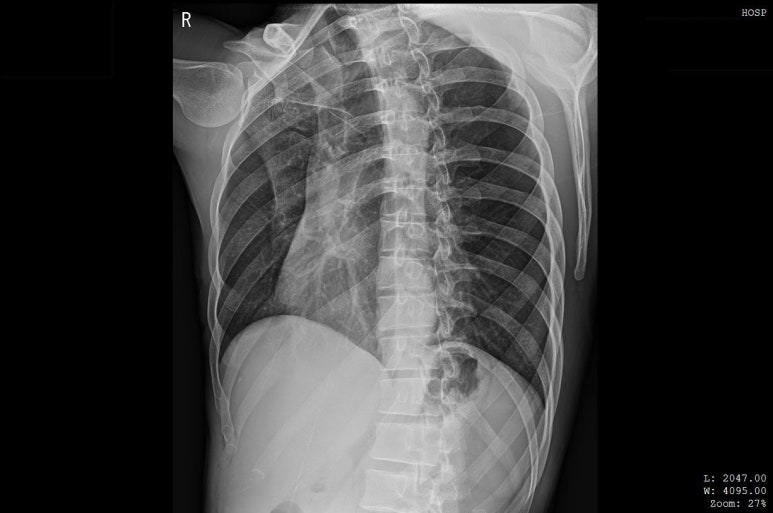

해당 환자분의 X-RAY 영상, 골절선이 보이지 않습니다.

병원에서 X-ray상

뼈는 멀쩡하다고 합니다.